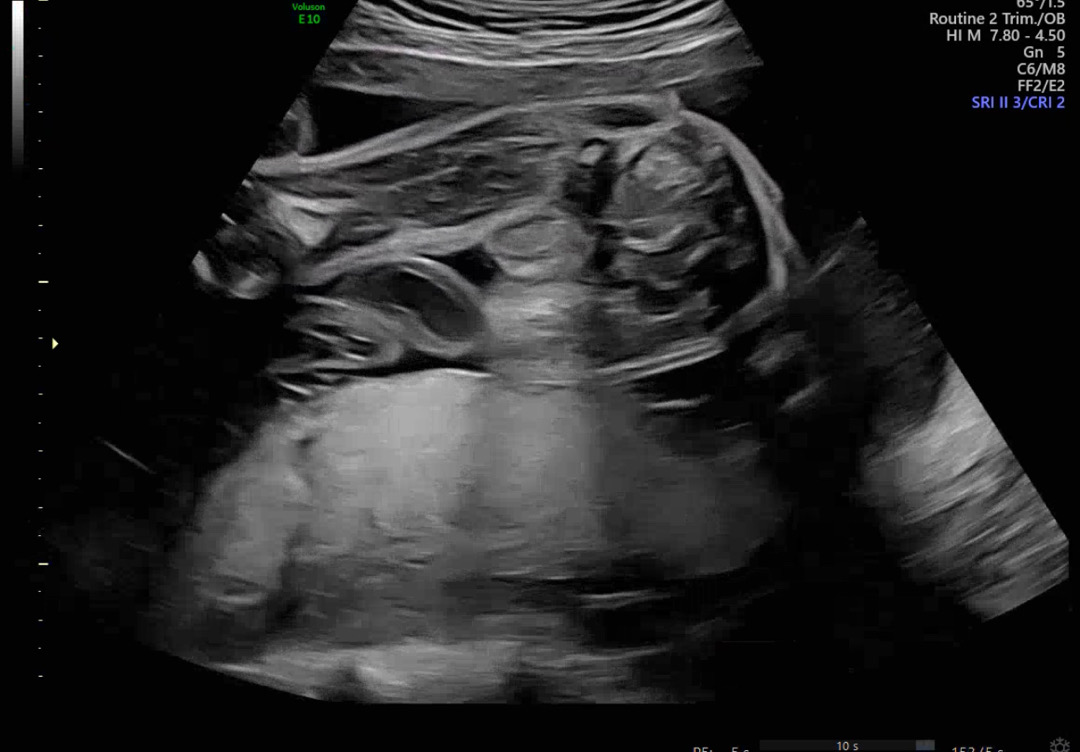

대음순일까요 고환일까요?

25주때 찍은건데 그전에는 계속 다리로 못보게 가리다가 저날 드디어!!! ㅋ다리사이를 보게 됐어요 ㅋㅋㅋ 근데 고환일까??? 싶어서요 ㅋㅋㅋㅋ 오늘 다시 초음파 보러가는데 마지막으로 딸이기를 기도해볼게요! ㅋㅋ

딸인거같아요 아들이면 고환 안에도 뭐가 보여요!!

딸인 거 같은데요? 가운데 갈라진게ㅋㅋㅋㅋ